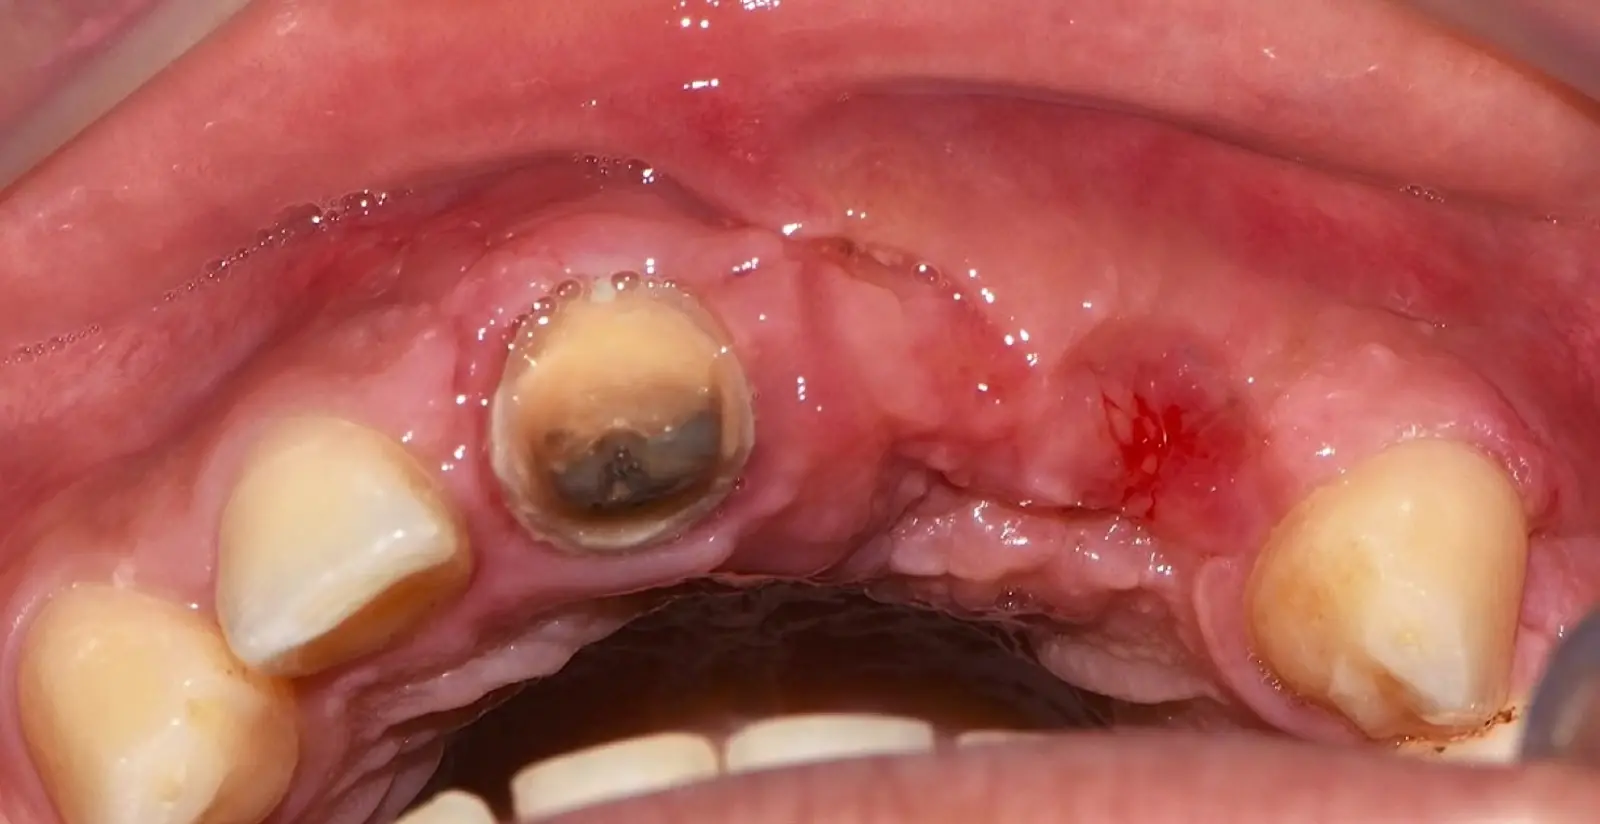

Figura 34. Vista frontal donde se observa deficiencia vertical del reborde óseo a nivel de las piezas 2.1, 2.2.

Figura 46. Control a los 10 días post cirugía.